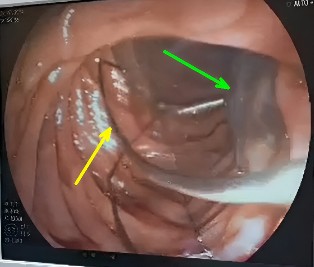

Figura 1 Canastilla extractora de cálculos del colédoco (flecha amarilla) y Fasciola hepatica (flecha verde)

Paciente mujer de 54 años procedente de la provincia de Paucartambo, con ocupación de agricultora y antecedente de crianza de ganado vacuno y ovejuno, ingresa al Servicio de Emergencia del Hospital Regional del Cusco por presentar desde hace seis días la siguiente sintomatología: tos, vómitos, cefalea, disnea a esfuerzos y malestar general, por lo que se decide internarla con el diagnóstico de neumonía adquirida en la comunidad (NAC). Una vez resuelto dicho cuadro, pasa al Servicio de Medicina Interna, donde se piden exámenes laboratoriales en los que se presentan alteraciones como urea disminuida en 11 mg/dl, leucopenia y un examen coproparasitológico en el que se observó presencia de huevos de Ascaris lumbricoides; además, se realiza una ecografía que indicó la presencia de coledocolitiasis. Por ello, posteriormente se le realiza una colangiopancreatografía retrógrada endoscópica, en la cual se observó en la segunda porción duodenal una papila única con apariencia fibrótica, y es debido a este hallazgo que se realiza una papilotomía y se extrae a la Fasciola hepatica (Figura 1), observándose sus movimientos ondulantes tras la extracción (Figura 2). Se concluye que se trata de un caso de fasciolosis ocasionado por Fasciola hepatica, para la cual la paciente recibe tratamiento con triclabendazol 10 mg/kg en una sola dosis por vía oral.